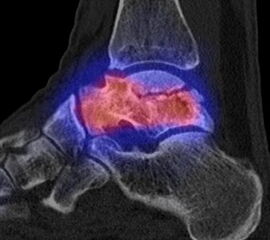

Die Abbildungen 4.2.a bis d zeigen den typischen Aspekt einer talacalcanearen Coalitio. Es besteht nur eine linksseitige, symptomatische Coalitio talocalcaneare (4.2.a und c); das 35 Tage zuvor angefertigte MRT zeigt keine auffälligen Signalveränderungen (4.2.b und d).

Abbildung 4.3. zeigt die Ursache für rechtsseitige Sprunggelenksbeschwerden bei einem Patienten mit talocalcanearen Coalitionen: nur die osteochondrale Läsion an der distalen rechten Tibia ist die Ursache des Schmerzes. Die bilateralen talocalcanearen Coalitionen sind asymptomatisch.